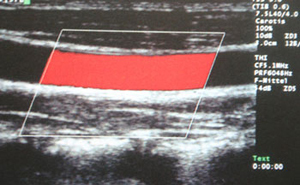

Ultraschallbild (Duplexsonographie):

normale Halsschlagader